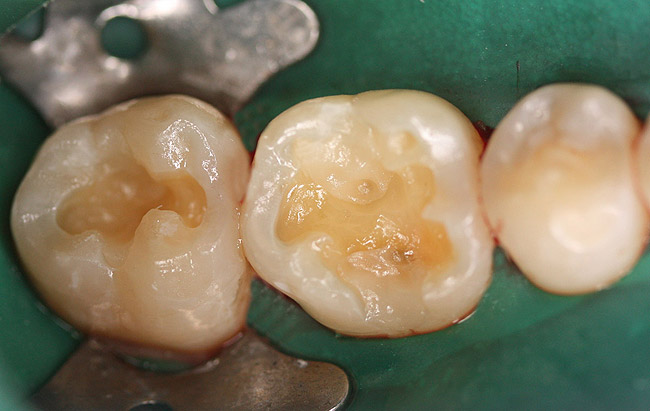

Case 1 (Figure 1 through Figure 6) reveals a mandibular first molar with severe wear and a defective amalgam. The amalgam and decay were removed, the tooth was prepared, and bonding to enamel and dentin was completed. An initial layer of composite was placed and cured, followed by many subsequent layers to minimize the negative effects of shrinkage. The composite was shaped and initial polishing was completed. Occlusion was adjusted, final shaping was accomplished and polishing was completed.

Figure 4. Restoration after placement of the final layer.

Figure 4